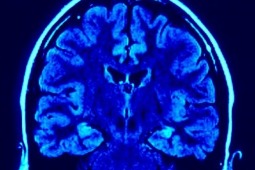

Półpasiec zwiększa ryzyko udaru mózgu

Badanie wirusologów z University College London, w którym udział wzięło blisko 320 tysięcy osób, dowodzi, iż zachorowanie na półpaśca zwiększa ryzyko udaru mózgu i zawału serca.

Naukowcy przebadali osoby w wieku 18-40 lat. Analizując wyniki doszli do wniosku, że zachorowanie na półpaśca w wieku do 40. roku życia zwiększa ryzyko wystąpienia w przyszłości udaru mózgu nawet o 74 proc., a zawału serca o 50 proc. Zaobserwowali też, iż ponad dwukrotnie wzrasta ryzyko przemijających ataków niedokrwiennych, tj. tzw. mini udarów. Choć badanie nie daje odpowiedzi, dlaczego półpasiec przyczynia się do zawału oraz udaru, to wynikające z niego wnioski, mogą być pomocne w profilaktyce schorzeń układu krążenia.